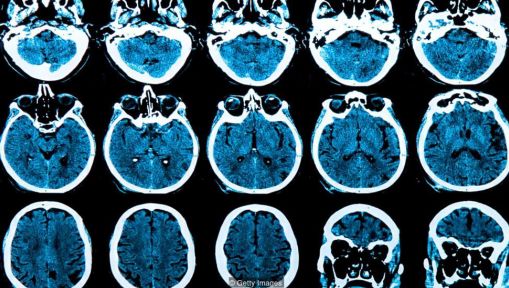

为了创造能像人一样思考的机器,计算机科学家们转向自然界来解决这个问题,创造了模仿大脑结构的算法,这是可以理解的。为了做到这一点,他们正在创建算法网络,这些算法被设计为像大脑中的神经元一样工作。当机器学习时,这些数学神经元之间的连接变形成集群。

全世界的医生都在越来越多的使用AI软件来检测癌症或眼部疾病的早期症状,但是最新研究成果表明,人工智能还能在一个人出现任何病兆之前的好几年,就预测到他是否会患上像阿尔茨海默病这样的疾病。